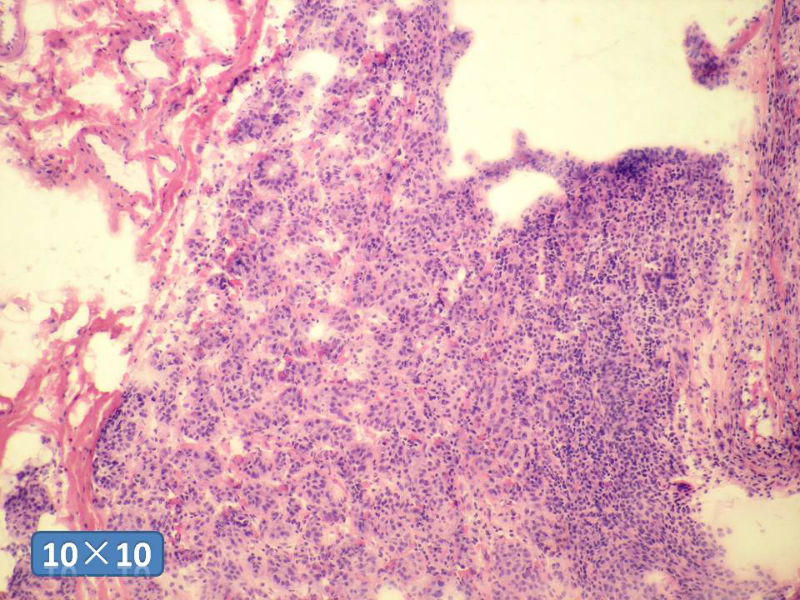

女性,50岁,乳腺肿物,冰冻切片(图1-25)

HE